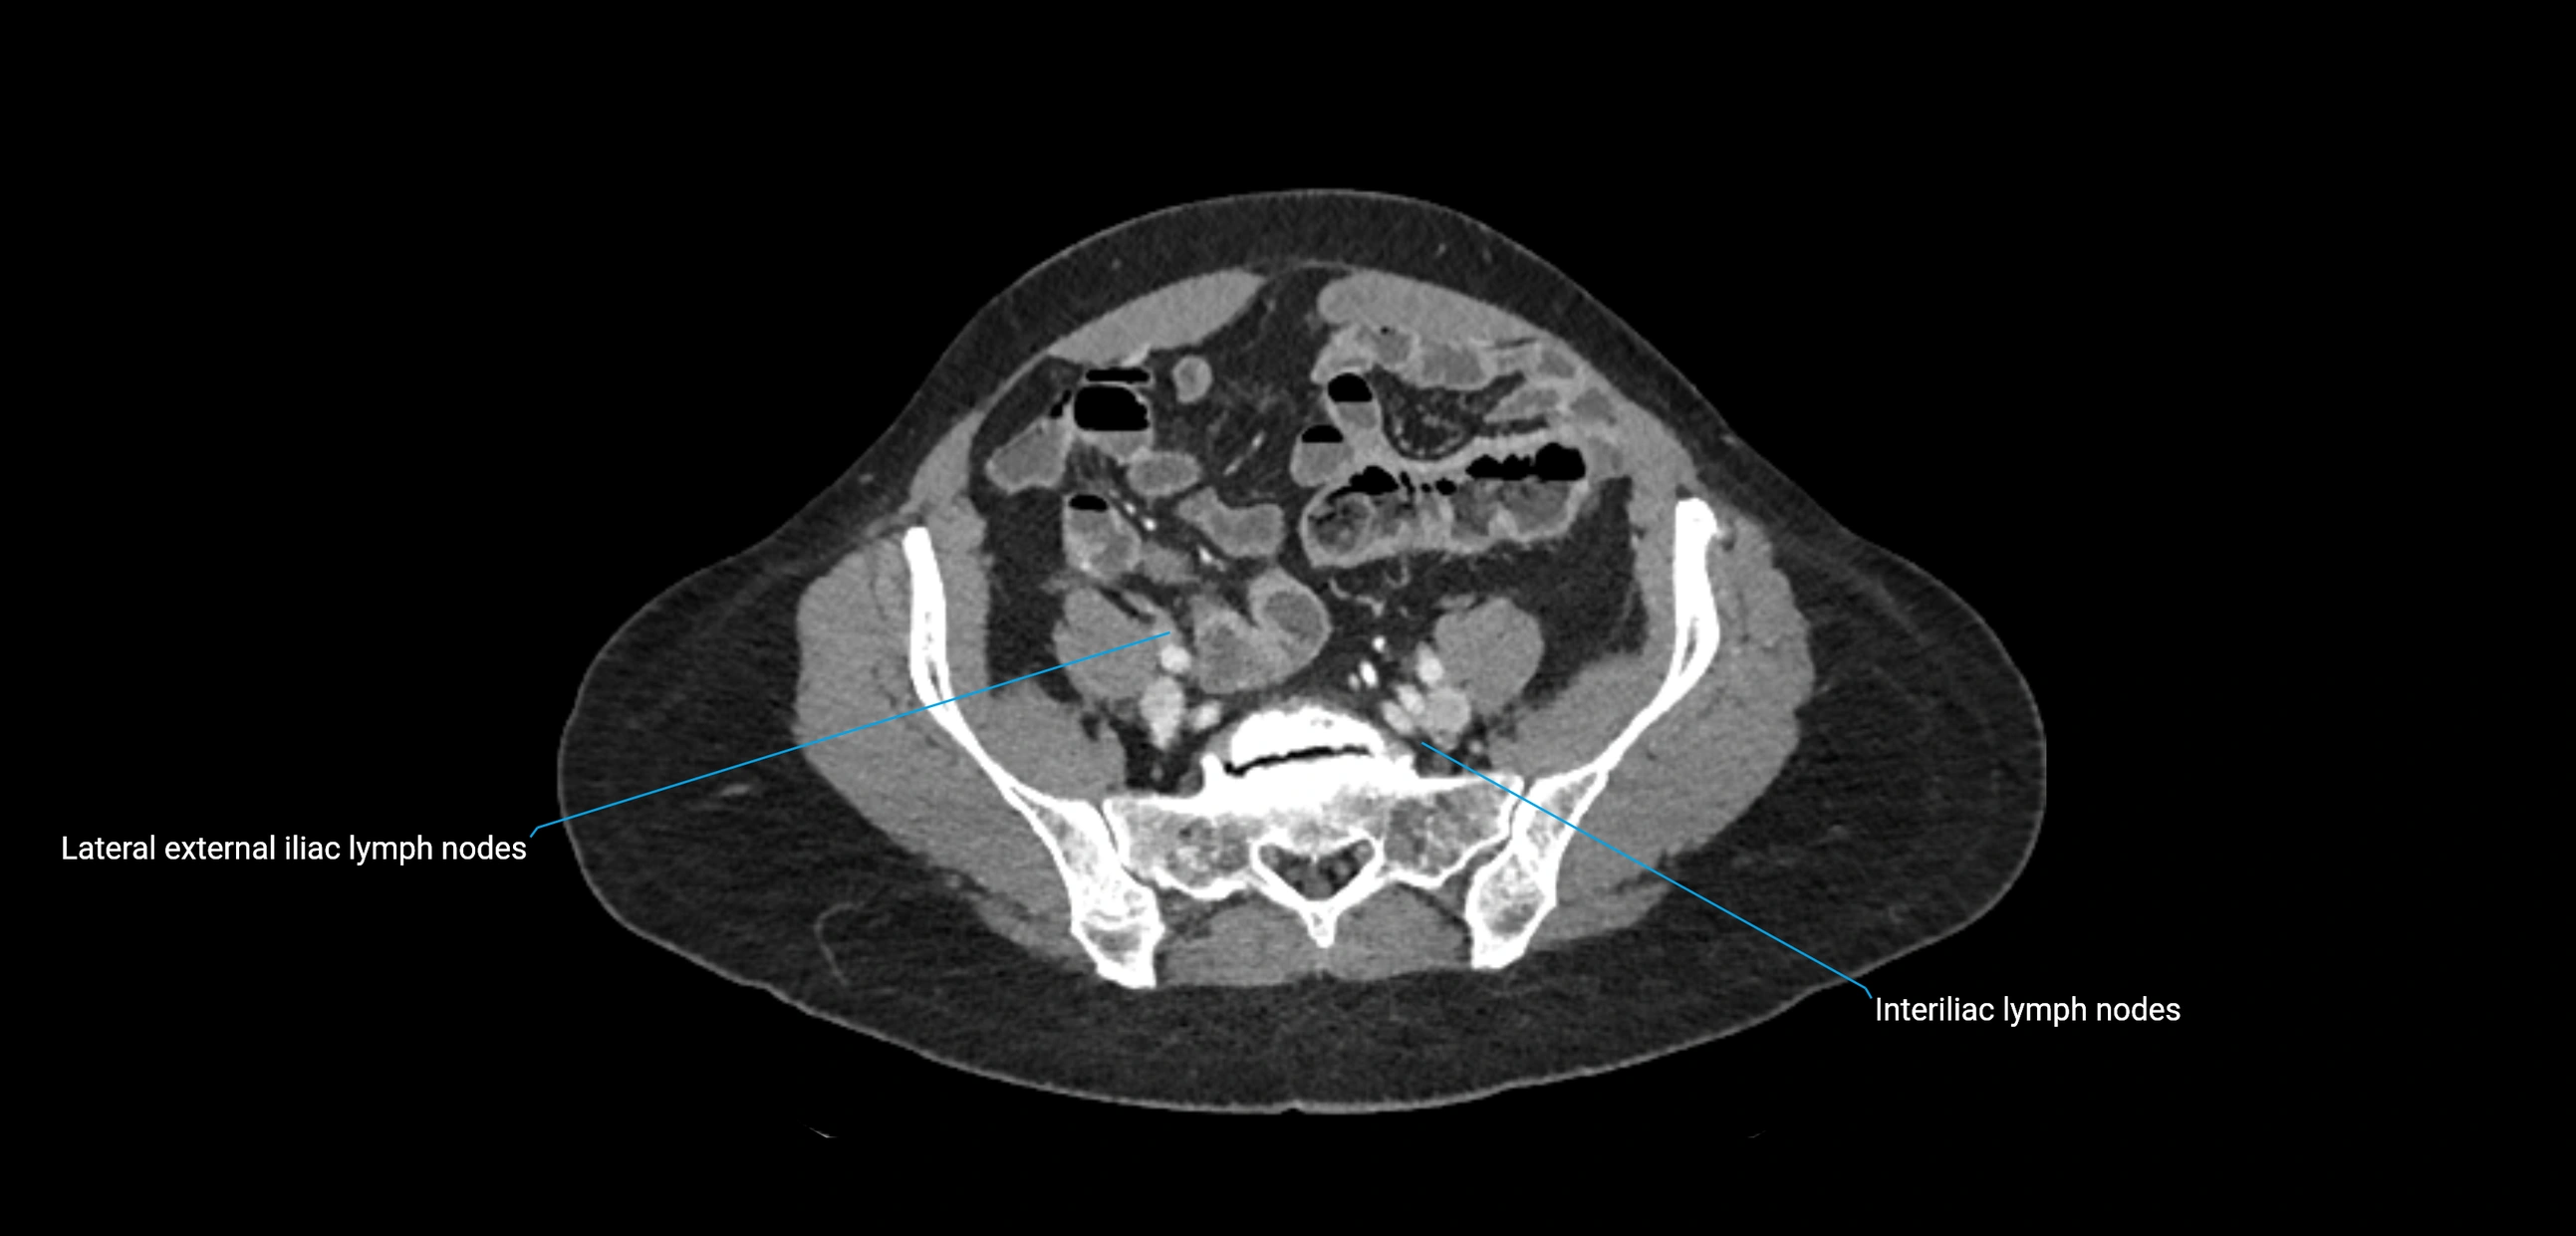

CT Appearance

CT Pre-Contrast:

• Nodes appear as soft-tissue density nodules adjacent to the aorta and IVC

• Calcification may be seen in chronic infections (e.g., tuberculosis)

CT Post-Contrast:

• Normal nodes enhance homogeneously

• Malignant nodes may show heterogeneous enhancement, central necrosis, or conglomerate formation

• Size >1 cm short axis is suspicious, though morphology and distribution are equally important